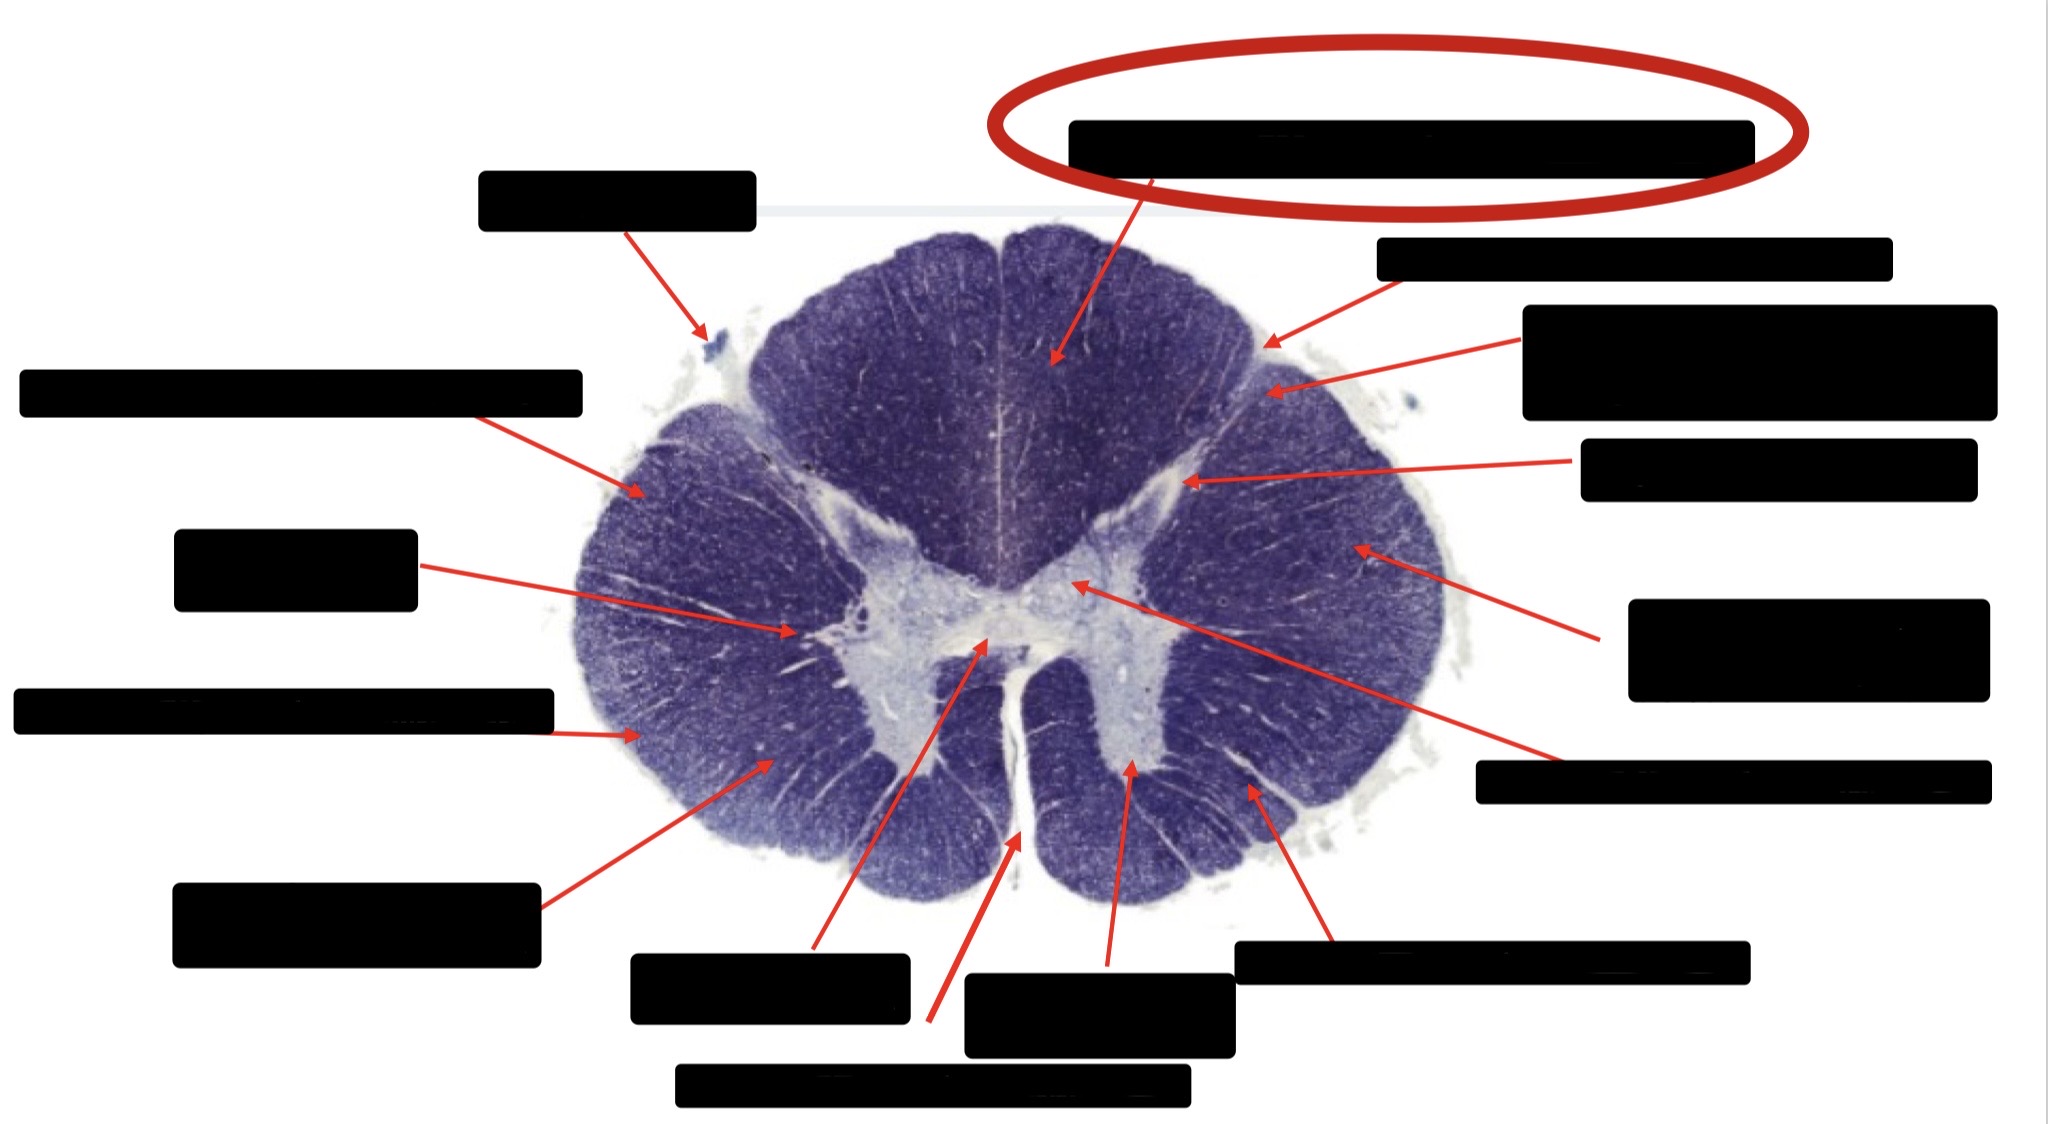

Posterior Column

Large Fiber Entry Zone

Posterior Spinocerebellar Tract

Clarke’s Nucleus

Anterior Spinocerebellar Tract

Ventral Root Fibers

Central Canal

Lissauer’s Tract & Small Fiber Entry Zone

Substantia Gelatinosa

Lateral Corticospinal Tract

Spinothalamic Tract

Anterior Horn Motor Neurons (Distal Muscles)

Anterior Horn Motor Neurons (Proximal Muscles)

Dorsal Rootlet

Lateral Horn